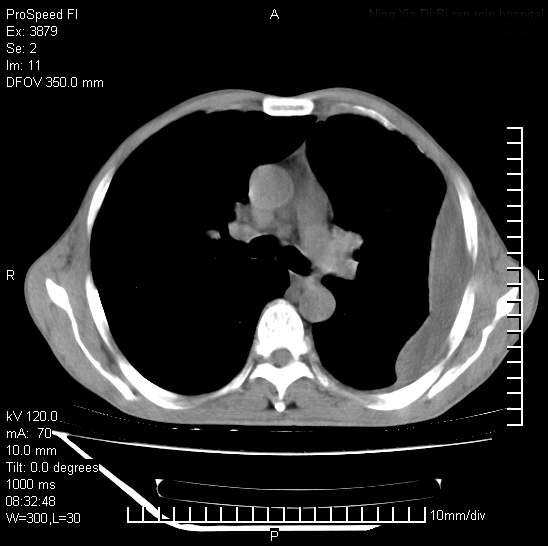

以下是引用37度在2008-6-6 11:20:00的发言:[br]1.包裹性积液,多考虑结核性;[br]2.穿刺术后改变。

以下是引用312nanyang在2008-6-6 15:12:00的发言:[br]基本支持楼主意见[br]疑问?左下肺支气管旁的软组织(16层)密度怎么解释?淋巴结还是斜裂胸膜增厚所致?能否增强进一步检查